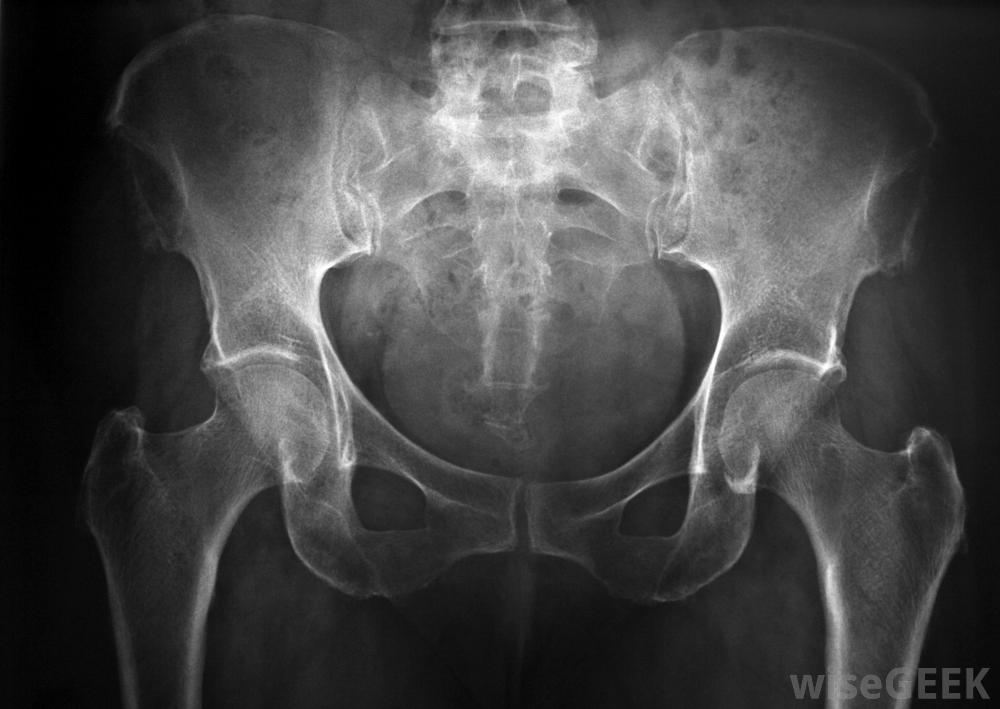

盆底功能障礙是一種常見的醫學疾病,可導致排尿、排便和性交困難。這種疾病與支撐骨盆器官的肌肉異常痙攣或控制問題有關。盆底功能障礙的人可能患有慢性便秘或排空障礙或者她的膀胱,因為肌肉不能正常工作。許多被診斷患有這種疾病的患者可以通過服用藥物和與治療師合作來學習如何加強和更好地控制肌肉。如果器官從薄弱的底板脫出或囊腫形成,可能需要手術前列腺肥大可引起盆底問題。許多不同的因素可導致盆底功能障礙在許多情況下,根本原因無法被發現。與大多數其他肌肉控制問題不同,盆底功能障礙似乎與神經系統疾病無關。骨盆的肌肉只是不協調的;病人可以控制他們的運動,但他或她不能使他們一致收縮以排便和排尿可能的原因包括分娩后肌肉和神經衰弱,前列腺突出,骨盆區域受傷。此外,排便時用力過猛會導致盆底肌肉受損X光可用于尋找與盆底功能障礙相關的問題。盆底功能障礙的癥狀可能因協調問題的程度和特定肌肉的不同而有所不同涉及。許多人排便困難,導致慢性便秘和頻繁但無效果的排尿沖動。當肌肉異常虛弱時,便是主要問題。女性在性交過程中也可能經歷嚴重疼痛,因為支撐陰道的肌肉無法放松正確。盆底功能障礙會導致排尿、排便和性交困難醫生通常可以根據病人的癥狀和全面的體格檢查來診斷盆底功能障礙。可以進行X光片和其他影像掃描,以尋找前列腺腫大、器官脫垂或肌肉缺損的跡象。醫生可以按壓下腹部,看看是否有壓迫感,以及有些情況下,可以用攝像機探頭觀察腸道或陰道內的肌肉運動盆底功能障礙患者可能患有慢性便秘。盆底問題可以通過幾種不同的方法進行治療。患有慢性便秘的患者通常使用肌肉放松和鼓勵運動,多喝水,多吃富含纖維的食物。另一種被稱為生物反饋的治療方法是一種物理治療技術,專家幫助患者了解控制不同肌肉的感覺。通過練習,許多人能夠獲得更好的協調性。如果問題持續存在,外科醫生可能需要手動將肌肉和器官固定到位,或面對其他潛在問題,如前列腺肥大。盆底功能障礙的癥狀因所涉及的特定肌肉而異。